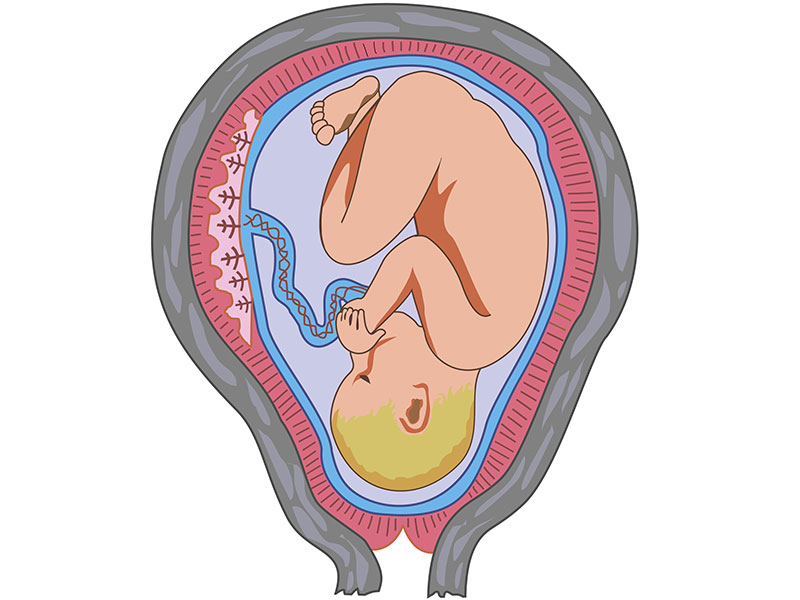

女性怀孕的时候,尤其是在分娩前,随着胎头慢慢下降进入骨盆,卵巢会分泌出一种叫“松弛素”的物质,使得骶髂关节、耻骨联合软骨及韧带变得松弛,耻骨联合及两侧骶髂关节出现轻度分离,从而使得骨盆出现暂时性的扩大,以利于宝宝的顺利娩出。